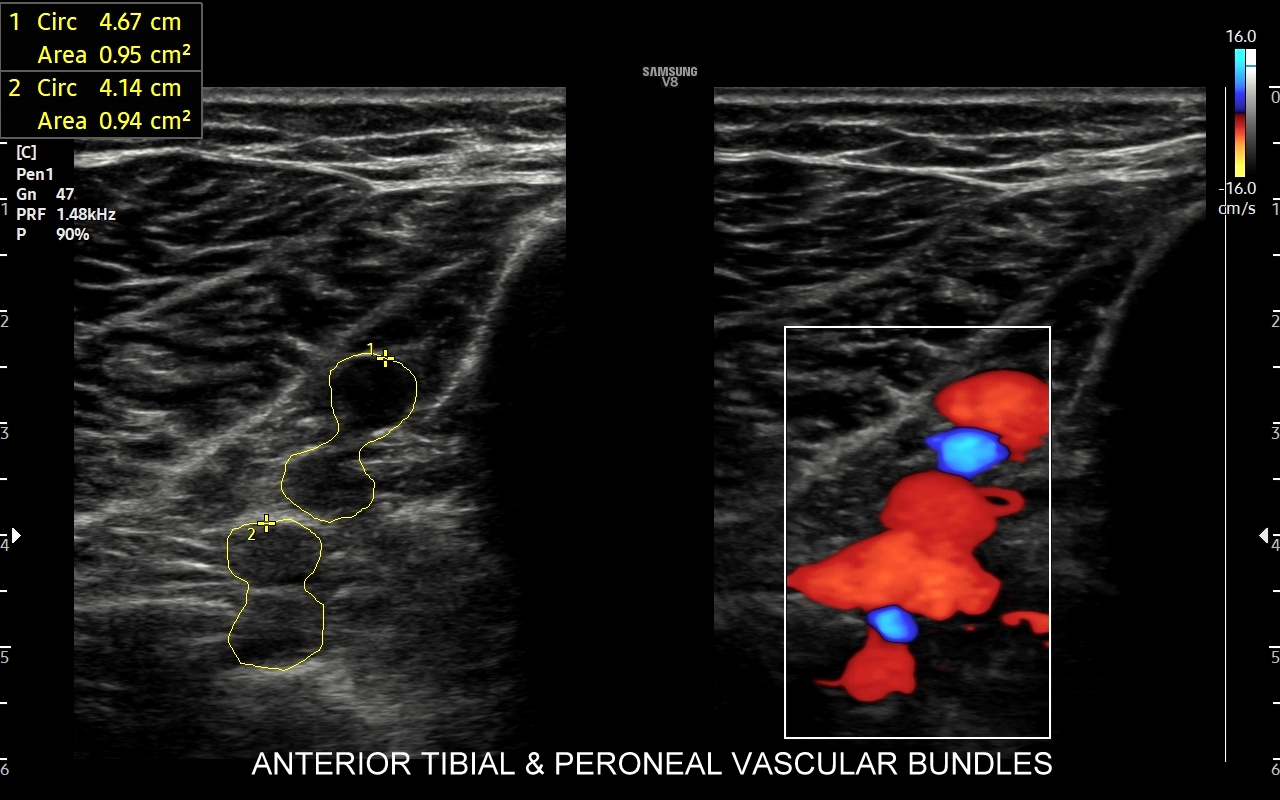

Badanie USG żył kończyn dolnych najczęściej wykonywane jest w ramach diagnostyki niewydolności żył powierzchownych oraz ich objawów w postaci pajączków żylnych, żylaków kończyn dolnych, obrzęków i owrzodzeń żylnych. Kolejnym pod względem częstości wskazaniem do badania Doppler żył jest podejrzenie zakrzepicy żył głębokich kończyn dolnych, monitorowanie leczenia zakrzepicy oraz ocena jej powikłań odległych. Powikłaniem nieleczonej zakrzepicy żył głębokich może być zespół pozakrzepowy manifestujący się masywnymi obrzękami kończyny i zaburzeniami troficznymi. Badanie USG Doppler żył kończyn dolnych często uzupełniane jest oceną układu żył centralnych w miednicy i jamie brzusznej. W tych obszarach również pojawiać się mogą żylne zmiany zakrzepowe, niedrożności żył, a nawet zmiany nowotworowe.

Podczas najczęściej przeprowadzanego badania, tj. USG Doppler kończyn dolnych, oceniane są żyły głębokie oraz powierzchowne na całej długości kończyny – od stóp aż do pachwiny. Czasami mogą zaistnieć wskazania do rozszerzenia badania na wyższy poziom układu żylnego, tj. na żyły biodrowe w miednicy i żyłę główną dolną w jamie brzusznej. Badanie USG żył jest badaniem dynamicznym, tzn. oprócz oceny wyglądu żył wykonuje się różnorodne próby czynnościowe, takie jak kompresja, głębokie oddychanie, próba Valsavy, podczas których rejestruje się przepływy krwi w żyłach.

W przypadku oceny wydolności żył oraz kwalifikacji Pacjenta do zabiegu na żyłach lub na żylakach kończyn dolnych dynamiczne badanie dopplerowskie żył wykonuje się także w pozycji pionowej. Przy opisanych próbach czynnościowych wykorzystuje się specjalne właściwości sprzętu USG, tj. tryby badań dopplerowskich, tryby duplex i triplex, a także angografię sonograficzną dostępną w aparatach wysokiej klasy.